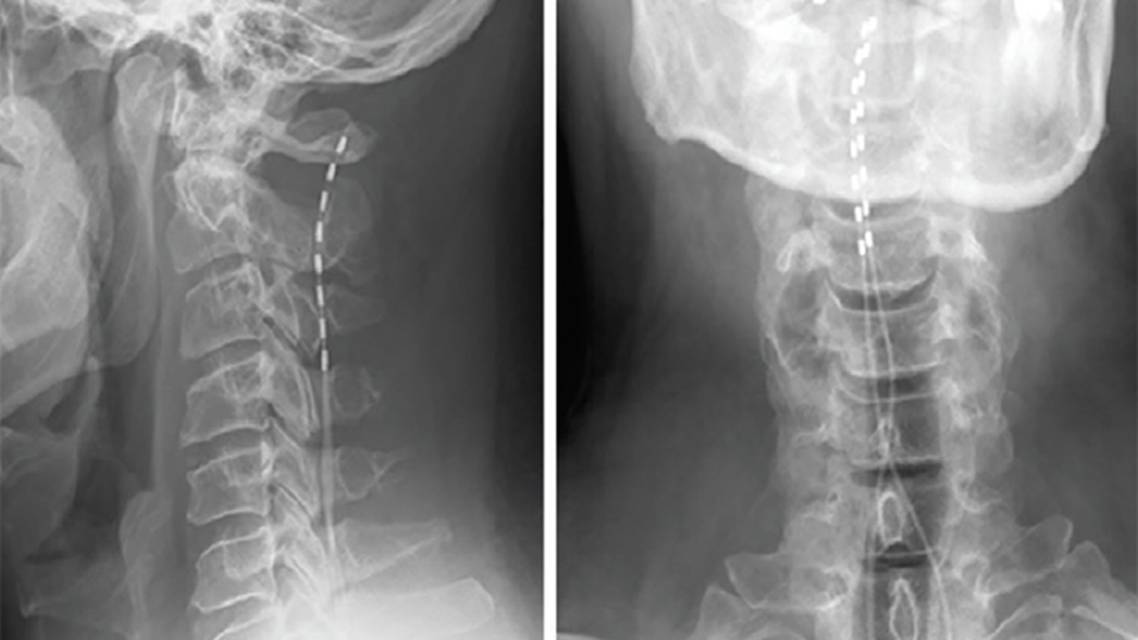

SCS electrodes comprise an array of metal contacts that generate a therapeutic electric field when programmed in combinations of anodes (positive) and cathodes (negative).4 Despite decades of clinical use and research, the underlying mechanism is not well understood. The gate control theory of spinal cord pain transmission posits activation of large-diameter fibers inhibits smaller-diameter fibers that carry pain signals.5 Although studies show SCS is more complex than simple pain gating explains, discovering modifiable pain pathways created a paradigm shift from ablative surgery to neuromodulation.

SCS has been studied and used to treat many presentations of chronic pain, most commonly in the context of postlaminectomy syndrome, or failed back surgery syndrome, and CRPS. Patients are required to have an external trial first, during which device settings can be adjusted and optimized.

Traditionally, SCS used tonic stimulation, producing parasthesia—a tingling sensation meant to overlap a person’s somatotopic pain distribution. Low-frequency stimulation at 40 to 100 Hz produces tonic stimulation. In more recent paradigms, minimal to no paresthesias are felt, termed subperception, subthreshold, or paresthesia-free waveforms. These paradigms include high-frequency stimulation (>500 up to 10,000 Hz). The absence of paresthesias suggests that there is no neuronal activation of dorsal column fibers,10 contradicting the gate control theory. Burst stimulation is another new paradigm, hypothesized to mimic innate neurologic activity.

Tonic SCS was considered more effective for limb than axial pain; however, both high-frequency and burst paradigms alleviate chronic back and leg pain more effectively than tonic SCS.11 More recent advances include dorsal root ganglion stimulation, a more targeted therapy for specific nerve root distributions of pain. In a randomized controlled trial, dorsal root ganglion stimulation was superior to conventional dorsal column SCS for lower extremity pain in CRPS lasting up to 12 months.12,13